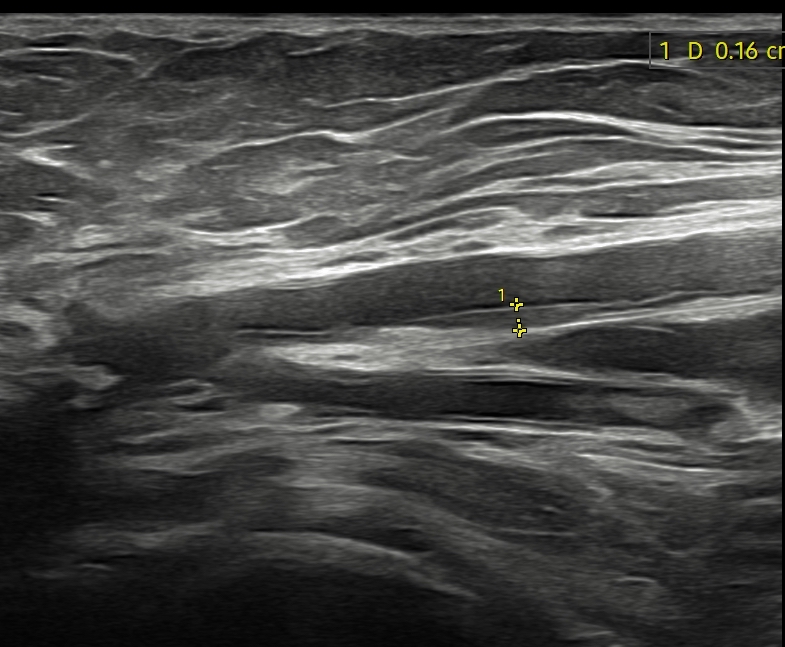

Dado el acceso a ecografía clínica en el centro de salud, se realiza la misma.

Hallazgos ecográficos

Se identifican placas de ateroma en ambas arterias femorales comunes, con pérdida del flujo diastólico, hallazgo sugestivo de enfermedad aterosclerótica significativa.

Los engrosamientos parietales difusos o focales sugieren aterosclerosis. En territorios de alta resistencia, el flujo normal es trifásico: un pico sistólico anterógrado, una corta fase reversa por resistencia periférica y un componente diastólico anterógrado de baja velocidad. El flujo arterial sano es laminar, con velocidades habitualmente menores de 1,5 m/s. Las estenosis hemodinámicamente significativas reducen más del 50% de la luz vascular y producen aliasing en Doppler color, con velocidades superiores a 1,3 m/s. Distalmente a una estenosis grave, los flujos se vuelven monofásicos, variando su resistencia según la vasodilatación distal.